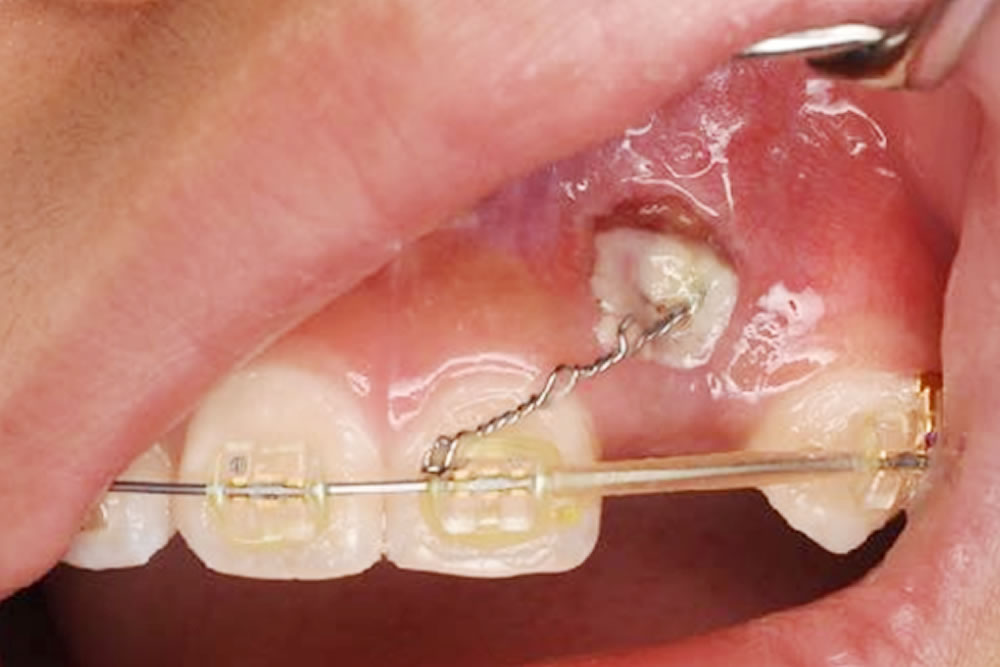

本症例では、残念ながら自然と萌出してくることがなかったため、矯正装置を変更し、マルチブラケット装置によるワイヤー矯正によって開窓牽引を行いました。

①CT画像にて外科的侵襲が最小限になるよう、開窓する部位を計画します。表面麻酔、浸潤麻酔をした後、電気メスにて歯肉を切除していきます。